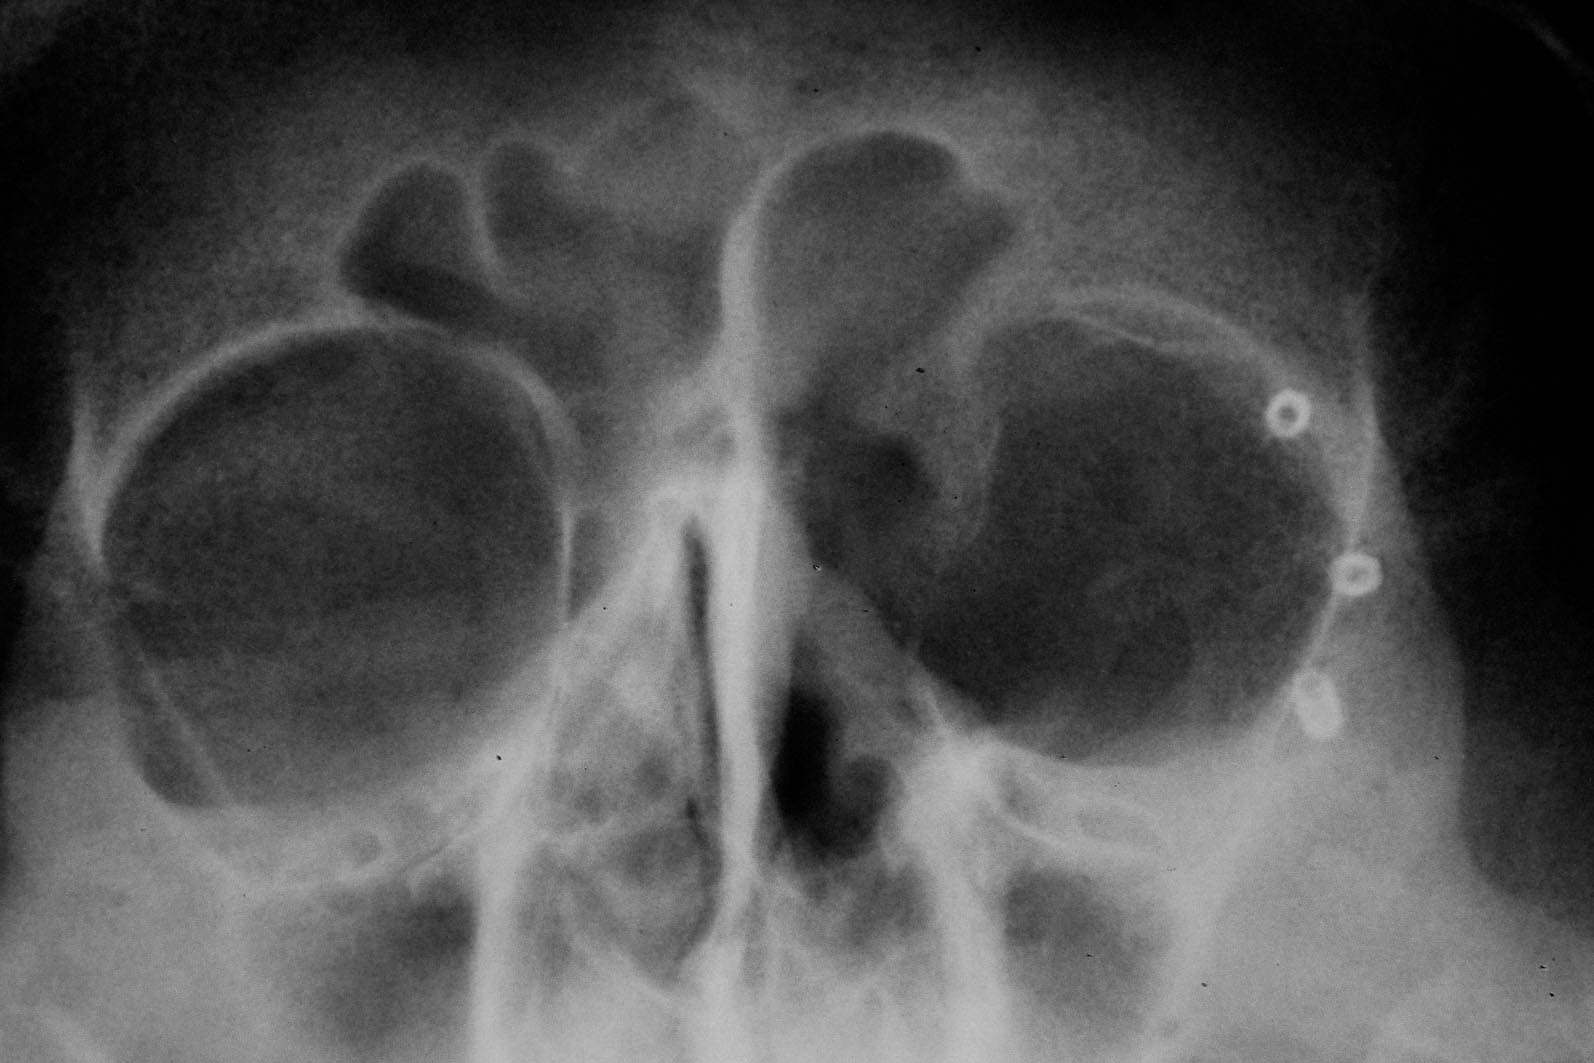

Chory po resekcji tkanek/narządów twarzoczaszki wymaga wnikliwej diagnostyki obrazującej zakres ubytku oraz stan podłoża kostnego. Wykonuje się zdjęcia radiologiczne RTG pantomograficzne szczęk OPG, konwencjonalną tomografię komputerową CT, stożkową tomografię komputerową CBCT, ukazującą trójwymiarowy obraz twarzoczaszki, oraz w razie potrzeby rezonans magnetyczny NMR. Możliwy jest również druk modeli 3D w skali 1:1 dowolnej części twarzoczaszki.

Diagnostyka ma za zadanie wykluczenie wznowy wyciętego nowotworu oraz pomoc w ocenie tkanki kostnej w okolicy ubytku. Ocena kości pozwala na zaplanowanie zabiegu wszczepienia implantów jako przyszłego fundamentu niezbędnego dla mocowania protez poresekcyjnych lub epitez twarzy.

Zastosowanie współczesnych technik obrazowania trójwymiarowego umożliwia precyzyjne zaplanowanie pozycji implantów czaszkowych, tak by ektoprotezę stabilnie osadzić na podłożu.